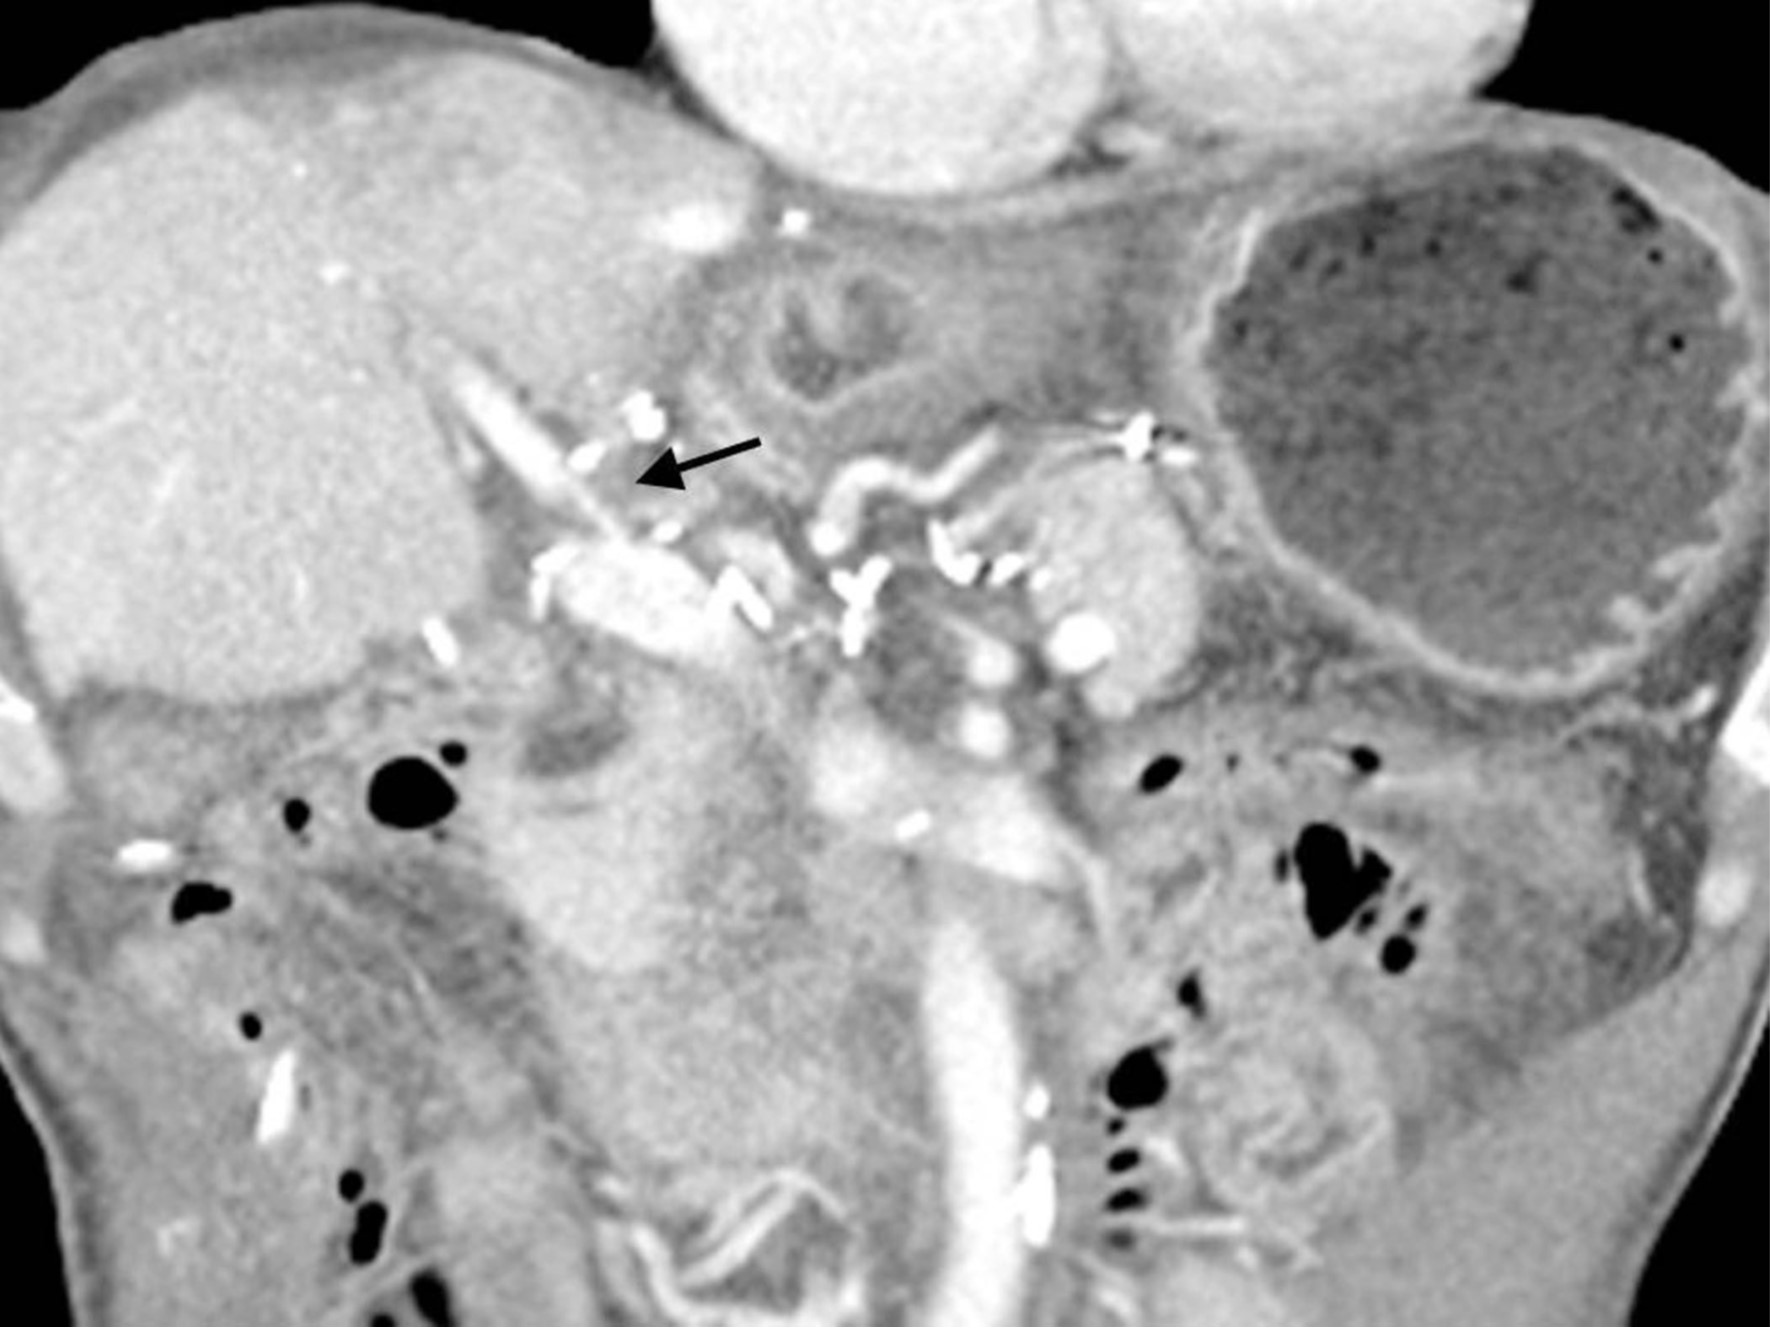

초음파 유도하에 비장정맥(splenic vein)을 천자하여, 8Fr sheath를 삽입하였음. Sheath를 통한 간문맥조영술(splenoportography)에서, 우전문맥(right anterior portal vein)의 심한 협착을 확인하였음(Fig. 2A). 이후 guidewire를 사용하여 우전문맥을 선택한 뒤, 6x40mm의 Stent(Zilver; Cook Medical, Bloomington, IN)를 삽입하였고, 남은 병변에 대해서 6x40mm balloon(Ultrathin Diamond;Boston Scientific, Natric, MA)을 이용하여 혈관성형술을 시행하였음. 이후 시행한 간문맥 조영술(Portal venography)에서 협착의 호전을 확인할 수 있었음(Fig. 2B). 삽입한 sheath의 지혈을 위해서, Histoacry(N-butyl-cyanoacrylate, B.Braun,Germany)과 lipiodol(Lipiodol Ultrafluid, Andre Guerbet, Aulnay-sous-bois, France)의 혼합(mixture, 1:4) 2cc로 tract embolization한 후 시술을 종료하였음.

1주일 후 시행한 복부 CT에서 우전간문맥의 스탠트는 혈류가 잘 유지 되었음(Fig. 3).

Fig. 3.

Fig. 3. Follow up CT after 1 day demonstrates good patency of portal stent.